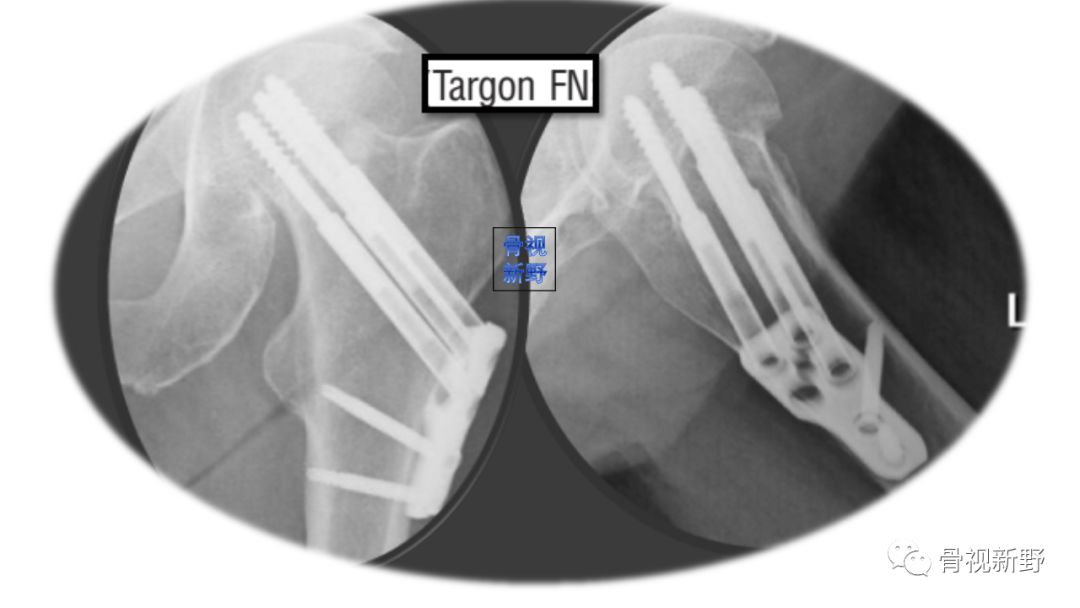

优化固定新理念——角稳定滑动髋钢板(Telescoping hip plate)

该固定方式将角稳定与滑动加压结合起来。但文献报道:骨不连/再移位:15.4%;头坏死:11.1%;转THA:20.7%[Mir 2015]。

(Telescoping hip plate)

与Targon FN相似,是Zimmer Biomet研发的新产品,尚需多中心临床对照实验验证。